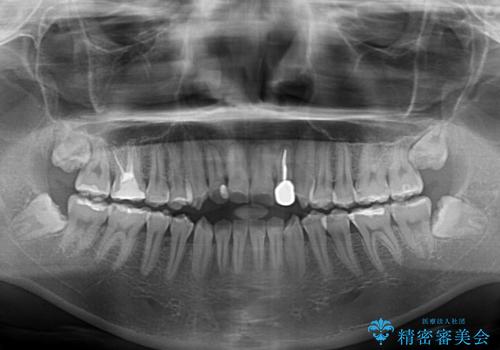

開咬を治す インビザラインによる矯正治療

- 上下前歯の開咬を気にして来院された患者様です。

開咬はインビザラインを用いると有意に改善ができるため、インビザラインによる矯正治療を行うこととしました。

途中1年8ヶ月ほど来院されず、久しぶりの来院後は治療が面倒とのことで、前歯の叢生や隙間に不十分な点が残った状態での終了となりました。